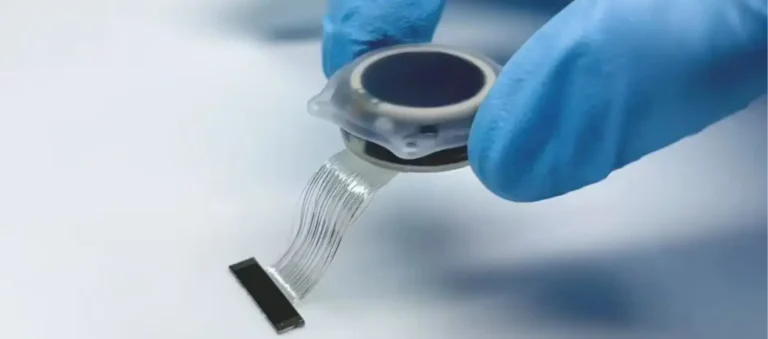

فناوری نوین «عصبزدایی لگنچه کلیه»؛ رویکردی جدید برای درمان هدفمند فشار خون بالا شرکت وِرو مِدیکال (Verve Medical) با معرفی فناوری نوآورانه «عصبزدایی لگنچه کلیه» (Renal Pelvic Denervation یا RPD)، گام تازهای در درمان بیماران مبتلا به فشار خون کنترلنشده برداشته است؛ رویکردی که میتواند رقابت جدیدی را در بازار درمانهای مداخلهای فشار خون…